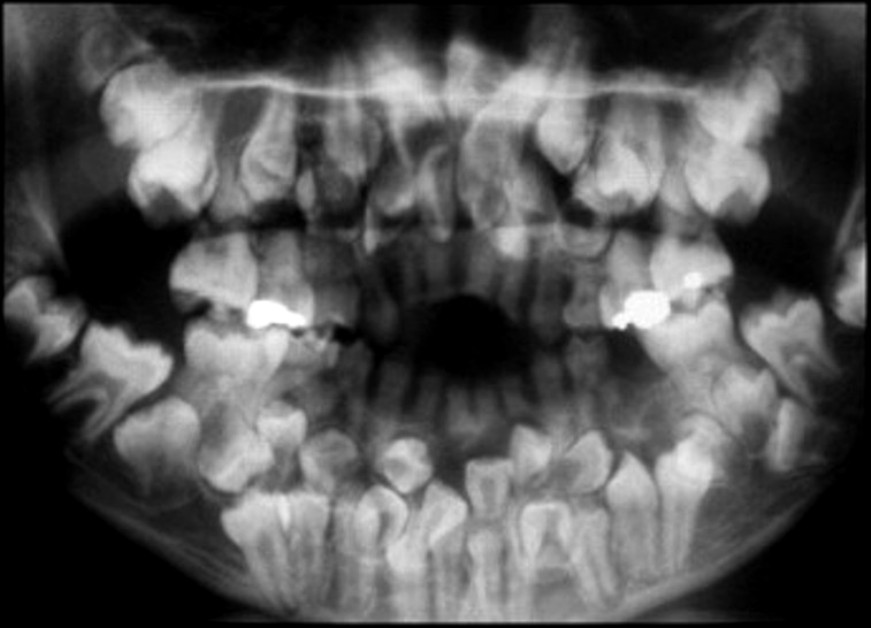

BELOW ARE X-RAYS OF ACTUAL PATIENTS

There is evidence of hereditary factors along with some evidence of environmental factors leading to this condition. While a single excess tooth is relatively common, multiple hyperdontia is rare in people with no other associated diseases or syndromes. Many supernumerary teeth never erupt, but they may delay eruption of nearby teeth or cause other dental or orthodontic problems. Molar-type extra teeth are the rarest form. Dental x-rays are often used to diagnose hyperdontia.

It is suggested that supernumerary teeth develop from a third tooth bud arising from the dental lamina near the regular tooth bud or possibly from splitting the regular tooth bud itself. Supernumerary teeth in deciduous (baby) teeth are less common than in permanent teeth.

When classified by position, a supernumerary tooth may be referred to as a mesiodens, a paramolar, or a distomolar.

The most common supernumerary tooth is a mesiodens, which is a malformed, peg-like tooth that occurs between the maxillary central incisors.

Fourth and fifth molars that form behind the third molars are another kind of supernumerary teeth.